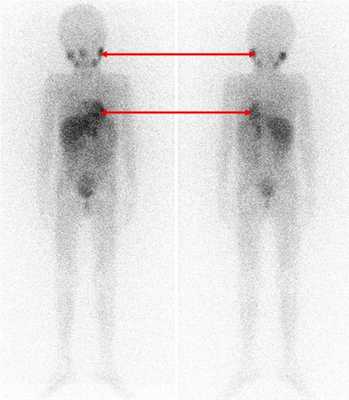

Одним из наиболее информативных специфических методов топической диагностики нейробластом является сцинтиграфия с метайодбензилгуанидином (МЙБГ), меченным 123I. МЙБГ по своей химической структуре сходен с катехоламинами в организме. Это вещество концентрируется в тех опухолях, которые вырабатывают катехоламины. МЙБГ метят радиоактивным изотопом йода (например, 123I) в безопасной для жизни дозе, и готовый препарат внутривенно вводят в кровоток. Накапливаясь в клетках опухоли, он дает излучение. Эти сигналы регистрирует специальная камера и переводит их в изображение. Таким образом, метод позволяет выявить не только первичную опухоль, но и наличие регионарных и отдаленных метастазов (рис. 7).

Рис. 7. Сцинтиграфия с метайодбензилгуанидином (визуализируется первичная паравертебральная опухоль с метастазами в кости черепа)